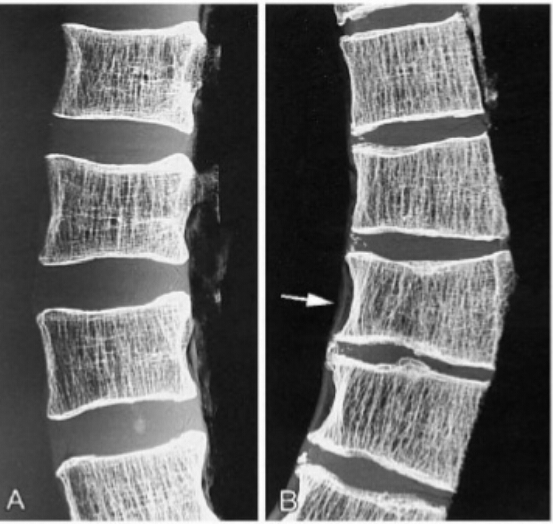

The patient is 70 years old. What is the dianosis? What are the radiographic features you see?

osteoporosis

radiographic features: cortical thinning, resorption of nonstress-bearing trabeculae, accentuated vertical struts, altered vertical shape (codfish deformity), schmorl’s nodes, endplate infractions